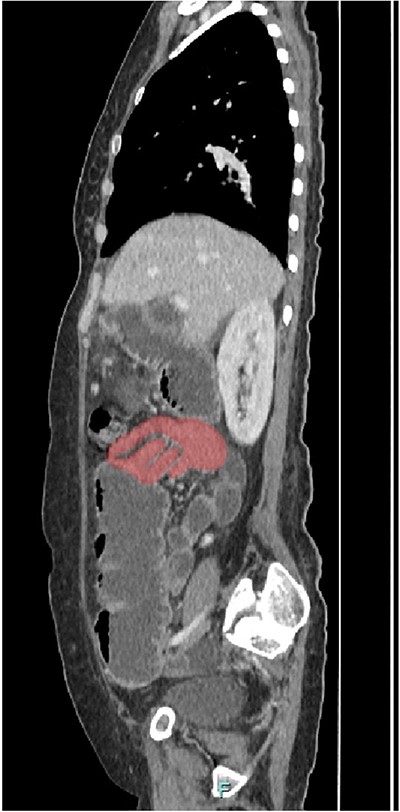

Her abdominal x-ray showed a dilated small bowel with a most likely transition point at the ileum and a collapsed large bowel (Fig. 1). Computed tomography (CT) of the abdomen showed an intussusception with the transition point at the proximal ileum with mesenteric invagination (Figs. 2 and 3).

Sagittal view of CT scan. The involved bowel loops are thickened with mesenteric invagination into the intussusception. The distal small and large bowel appears collapsed.